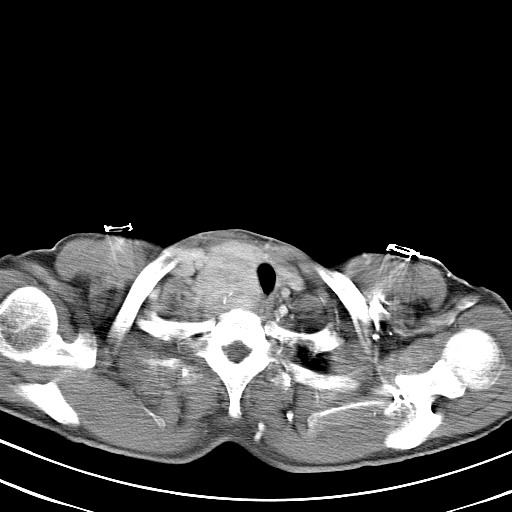

以下是引用汪涛同志在2007-8-2 0:40:00的发言:[br]病变虽然广泛,同时侵及双侧纵隔,但是无论左侧和右侧上下观察都是与右侧颈部甲状腺相延续的,而且强化幅度基本一致,又同时具有恶性病变病变的某些特征:肿块过大且密度不均,部分层面与正常纵隔结构分界不清,结合病史已有两年,考虑:胸内甲状腺肿恶变可能。[br]